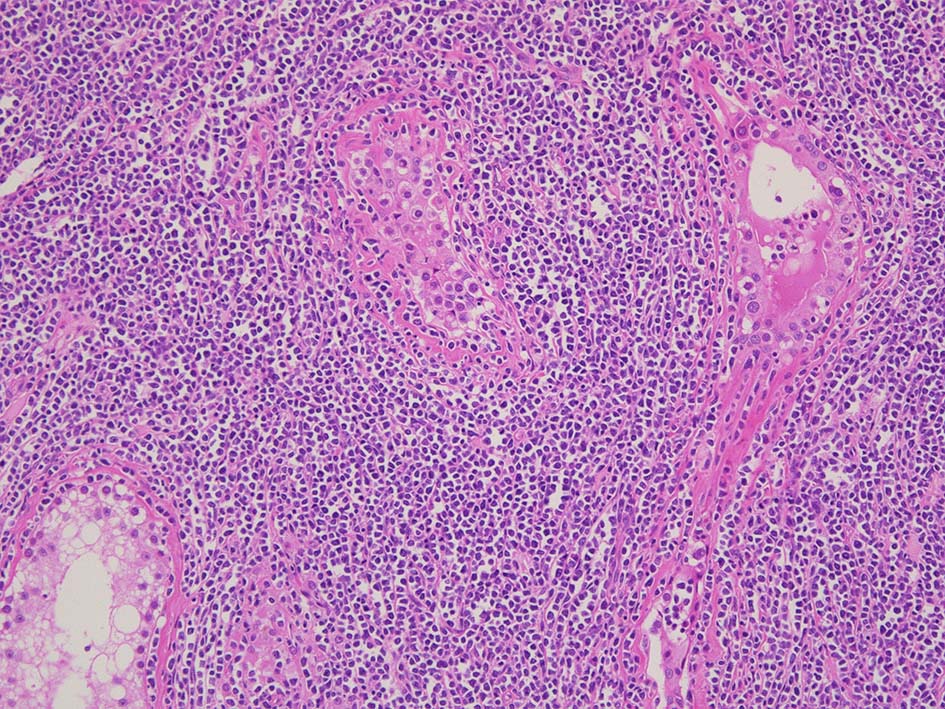

光顕所見; リンパ腫により, 少なくとも一部の領域の精細管が消失する. 末梢の領域では精細管の間質にリンパ腫細胞が浸潤する. ほとんどの場合、腫瘍細胞は精細管に侵入, 精細管の周辺を占め、生殖細胞とセルトリ細胞を中央に変位させるか, または精細管を完全に占拠してしまう.

腫瘍内に壊死が認められる. 異型リンパ球の密な増殖により精細管は消失している.

増殖巣では精細管は消失, 萎縮. 腫瘍境界部での浸潤所見がある.

精細管の多くがスペアされ, 間質にlymphoid cellsが密に浸潤している. わずかな精細管に浸潤が認められ萎縮や破壊像が認められる. 精細管において Lymphoepithelial lesion(LEL)に似た所見がある.